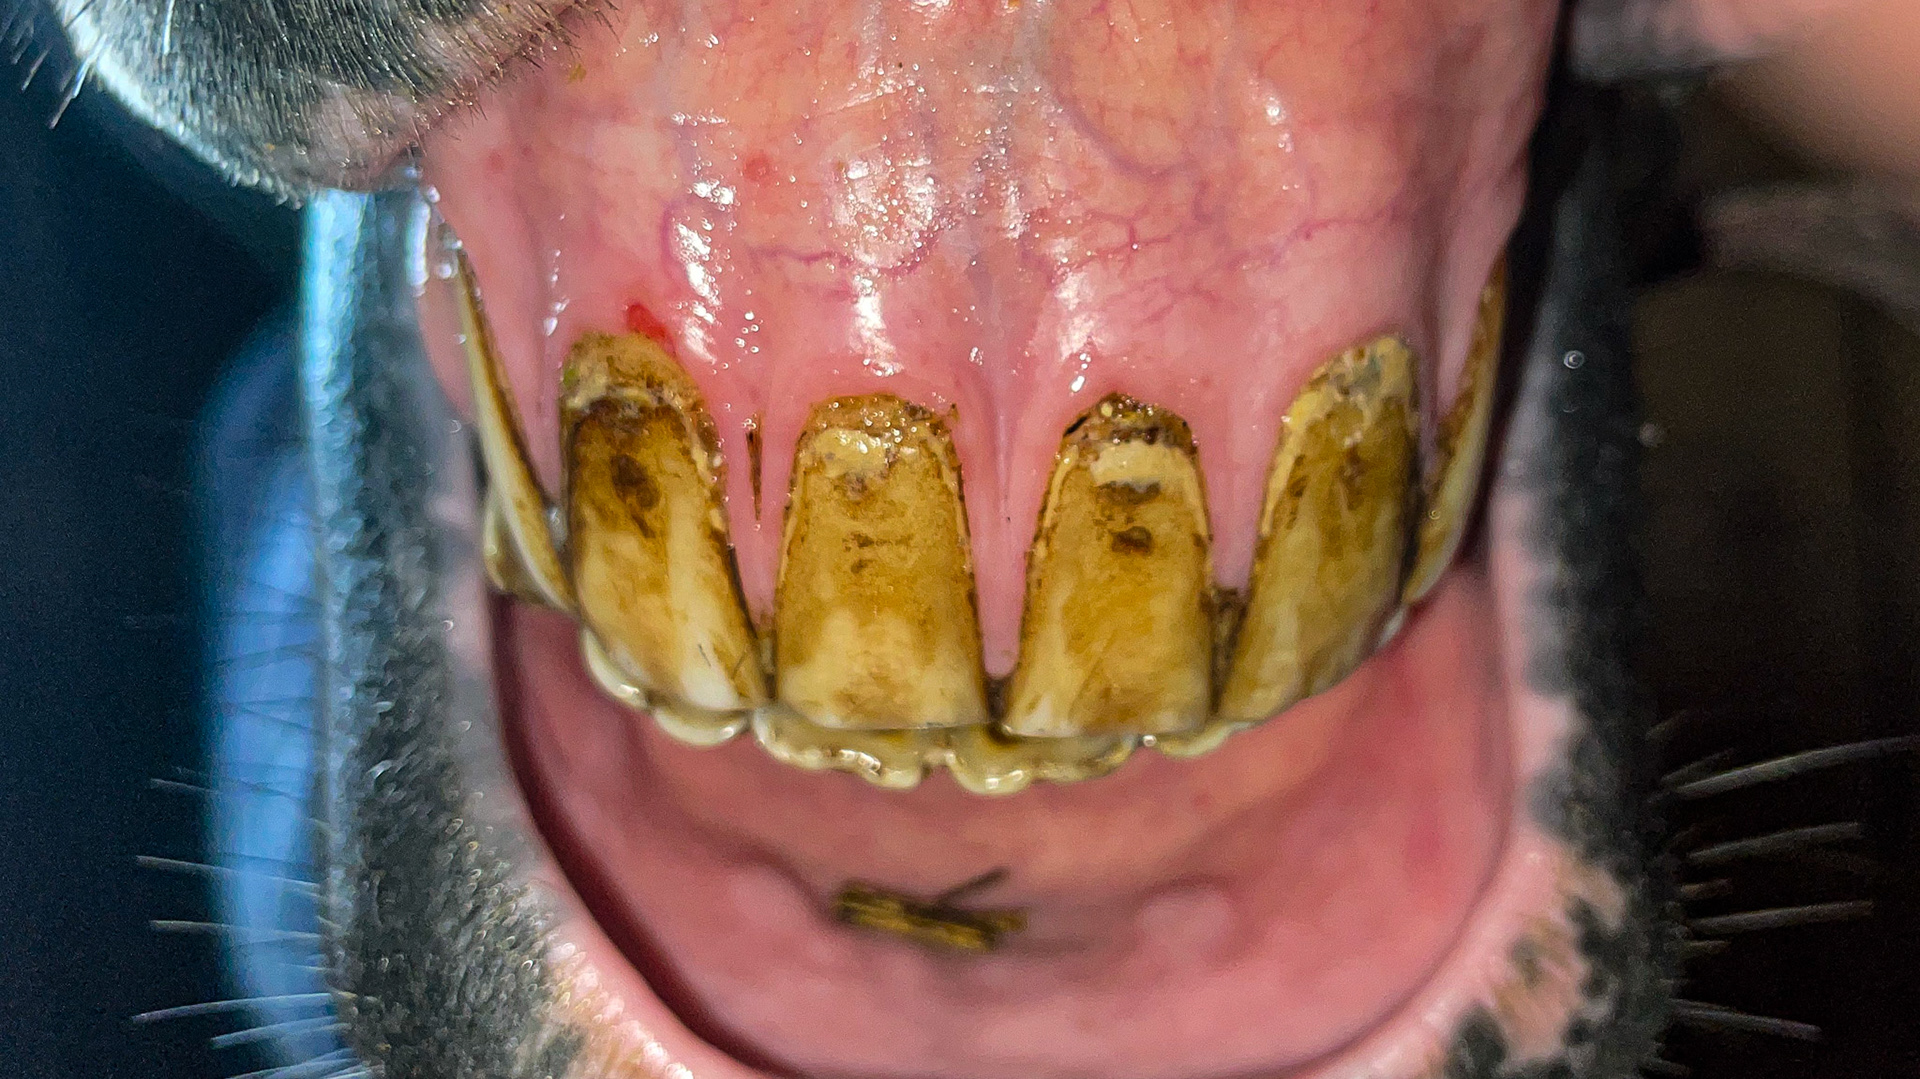

Advanced EOTRH with enlargement of the tooth roots. This is the horse in the radiograph in this section.